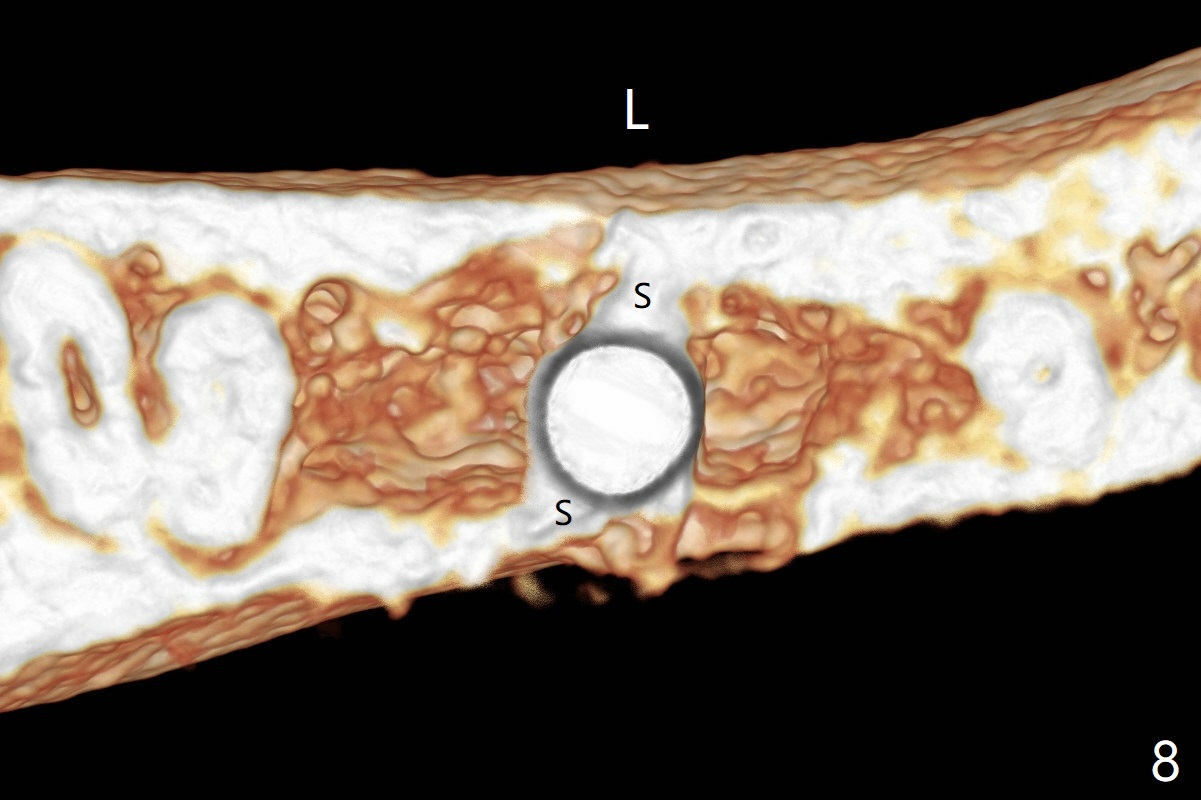

As planned, the crown of the tooth #30 with lingual (Fig.1 L) caries is removed and flattened with surgical handpiece so that the guide is able to be seated without interference. The osteotomy by 10.5 mm offset bone trimmer is lingual (Fig.2 white circle; due to in part the lingual caries and in part design error); in order to let the osteotomy to bounce back buccal, the part of the buccal roots are removed by surgical bur (arrows). The initial osteotomy by 2.2 mm drill is in the middle of the septum (Fig.3). After the last drill (3.5x11.5), the remaining roots are easily removed with proximators; a 4x11 mm dummy implant is placed with low stability and supracrestal lingual (Fig.4). Therefore a 4.5x9 mm final implant is placed with low torque. Following 4x11.5 mm drill, the torque increases to 20 Ncm. With insertion of healing screw, sticky bone (Fig.4 *: .5-1 mm cortical/cancellous allograft) is heavily packed around the implant (arrow), which apparently allows removal of the healing screw and placement of a 6x5.7(3) mm pair abutment without loosening the underlying implant. More bone graft is placed (Fig.6), followed by 2 pieces of PRF membranes. Although the implant is slightly buccally placed (Fig.7, due to over-removal of the buccal root, Fig.2 arrows), it is placed in the septum (Fig.8 S). To further compensate for the low implant stability, setting acrylic is applied in the edentulous area, particularly into the undercuts of the neighboring teeth (Fig.9 *) and around the abutment. The lingual margin of the acrylic dressing is extended (Fig.10 arrow) to cover the soft tissue defect associated with the lingual caries. As compared to the design (4x10 mm, Fig.11), the implant (4.5x9 mm, Fig.12) is placed buccal and ~ 2 mm deeper, reducing the chance of periimplantitis. The acrylic dressing is in place, but has mobility. The gingiva is healthy 2 weeks postop. The dressing is removed 1 month postop; the socket heals around the abutment buccal (Fig.13) and lingual (Fig.14). In spite of the immediate provisional, the abutment margin is substantially subgingival mesial 4 months postop, extremely difficult to take impression. A smaller diameter and longer cuff abutment is placed (Fig.15). The lingual gingiva heals normal 5 months postop, immediately before cementation (Fig.16).